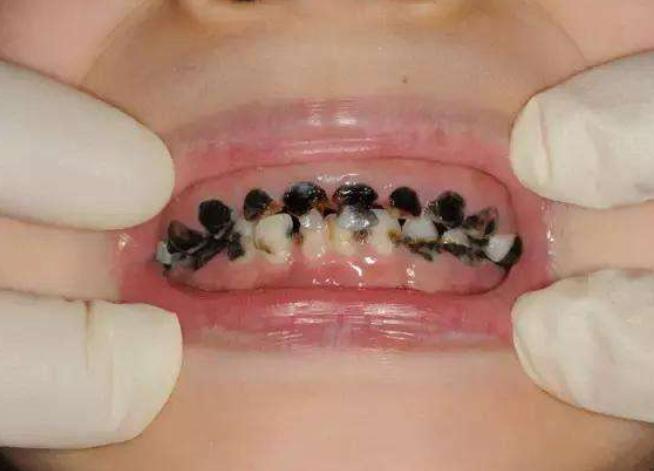

最近宝妈小晨发现自家宝宝的牙越来越黑,明明不到换牙的年龄,牙齿就开始脱落了。有些着急的小晨马上带着宝宝去医院做检查,发现孩子有轻微龋齿的问题。小晨认为,这与宝宝平时吃零食太多有关系,尤其是各种各样的糖果,每次不让孩子吃的时候,孩儿他爸总是偷偷给孩子拿,也是让人上火,这下好了吧,小小年纪牙齿就这么“烂”,以后可怎么办啊。但是医生给小晨的反馈,却让她有点意外。医生说:“宝宝的牙齿,可不是吃糖吃的”。

很多家长在宝宝小的时候,就非常忌讳给他们吃甜食,尤其是各种各样的糖果,孩子想都别想。因为妈妈们担心宝宝小小年纪,牙齿就出现问题,如果被蛀虫盯上,孩子的牙就危险了。不过,宝宝牙齿不好,与蛀虫有关,与细菌也有关。

成年人耐受的细菌,和宝宝们耐受的细菌可不是一回事。有些家长总喜欢给宝宝吃自己吃过的食物,虽然发生细菌感染的概率不大,但禁不住次数太多,时间太久。成年人口腔中的细菌进入孩子口中,就可能出现细菌感染,导致龋齿。